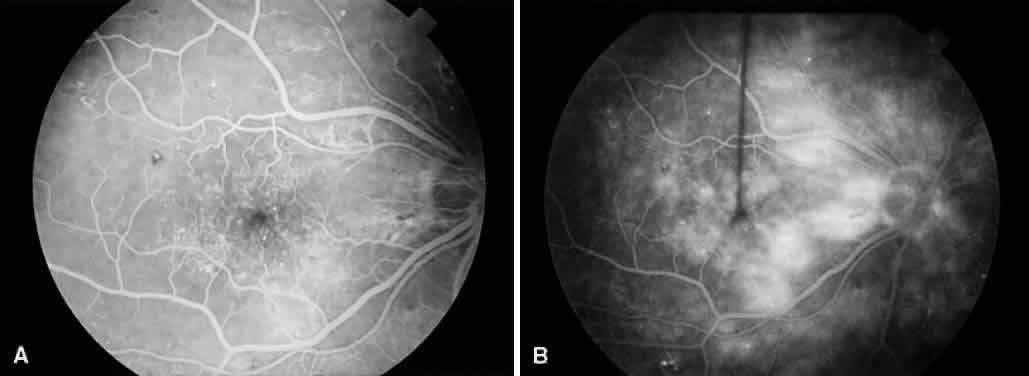

MACULAR EDEMA ASSOCIATED WITH POSTERIOR HYALOIDAL TRACTION

Although the ETDRS showed that focal macular photocoagulation is beneficial in the treatment of clinically significant diabetic macular edema, it has been observed that some patients with diabetic macular edema and a taut, thickened posterior hyaloid do not respond to macular photocoagulation. It has been hypothesized that vitreous traction may cause or exacerbate macular edema in these patients. Lewis and coauthors report the results of pars plana vitrectomy with separation of the posterior hyaloid in 10 eyes with diabetic macular edema and traction associated with a thickened and taut premacular posterior hyaloid.24 Preoperative fluorescein angiography showed a deep, diffuse pattern of leakage in the macula (Fig. 6). Nine of 10 eyes had previous macular photocoagulation, and only 1 of these eyes responded with a temporary decrease in macular edema. Postoperatively, vision improved in nine eyes, and macular edema resolved in eight eyes. Postoperative complications included vitreous hemorrhage, rhegmatogenous retinal detachment, cataract formation, and mild epimacular membrane (each occurring in one eye). Other studies also report visual improvement after vitrectomy and posterior hyaloid separation in such patients.25 Tachi and Ogino report the results of pars plana vitrectomy with separation of the posterior hyaloid in 58 eyes with diffuse diabetic macular edema without posterior vitreous detachment.26 These patients differed from those in prior reports in that they did not manifest a taut, thickened posterior hyaloid, and thus it is not clear whether the posterior hyaloid was responsible for the macular edema. Although these patients showed an improvement in macular edema and visual acuity, this study was not controlled and included only a few patients. Thus, it is reasonable to consider vitrectomy and posterior hyaloid separation in patients with diffuse diabetic macular edema associated with a taut and thickened posterior hyaloid, whereas the long-term efficacy of such surgery in patients with diabetic macular edema without vitreoretinal interface abnormalities has not been conclusively proven.

Fig. 6. A. Fundus photograph of an eye with vitreomacular traction syndrome. B. Fluorescein angiography showing deep, diffuse dye leakage.